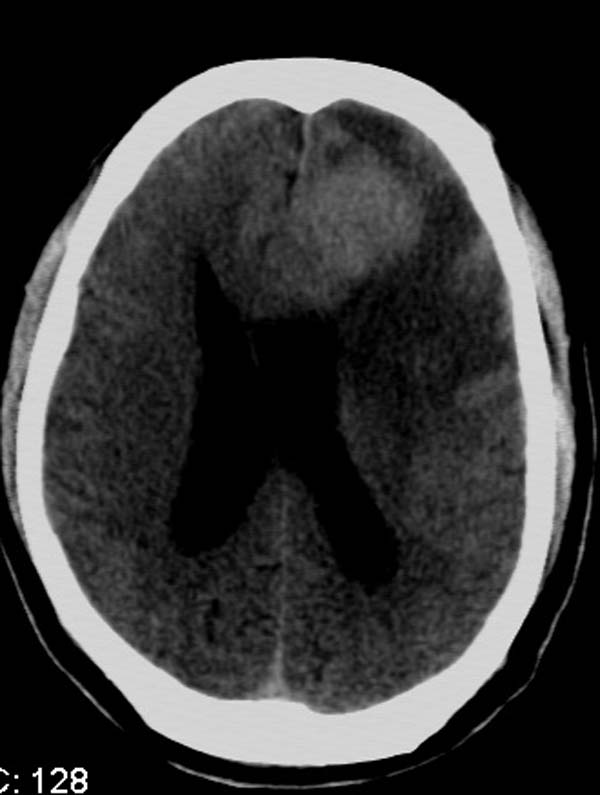

以下是引用拾荒者在2007-10-5 19:31:00的发言:[br]左额叶镰旁不规则形高密度影,中间见钙化灶及略低密度影,占位征象明显,周围有低密度水肿带环绕,首先考虑脑膜瘤。